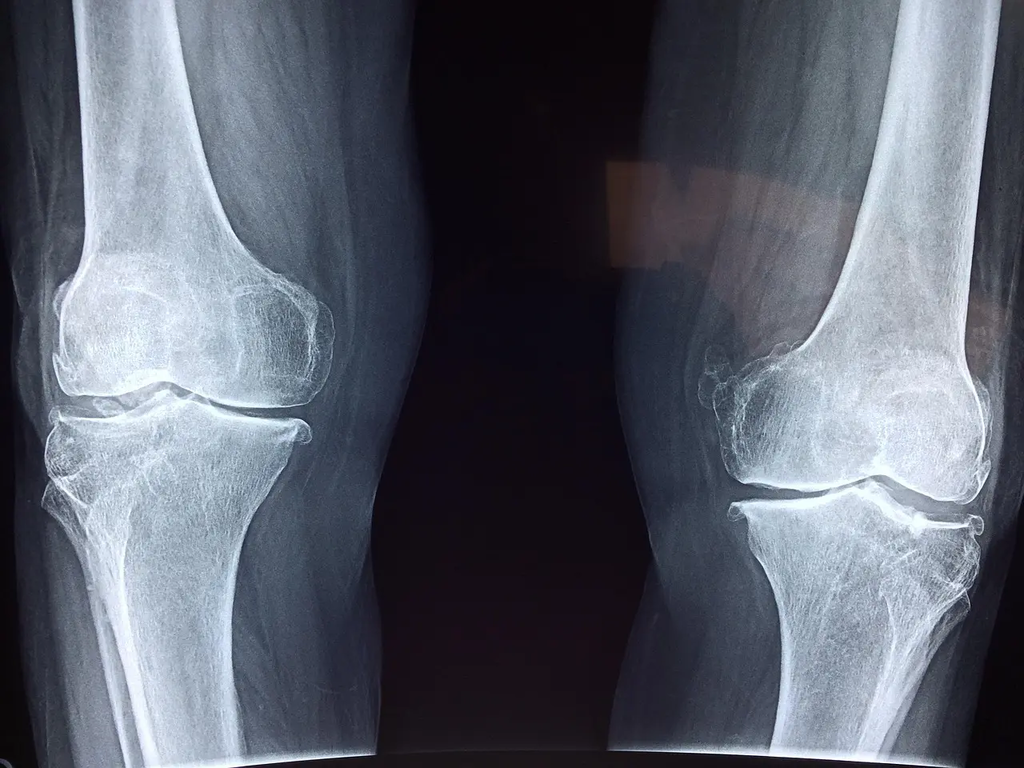

Bone density measures how much mineral is packed into bone. Higher density means stronger bones; low density can signal osteopenia or osteoporosis.

DEXA is a scan that measures bone mineral density to diagnose osteoporosis and assess fracture risk. Screening is commonly recommended for older adults and people with risk factors.